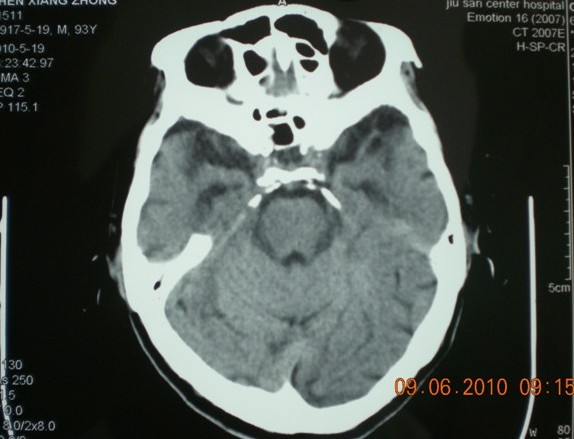

标题: CT27297:头晕 双下肢无力两天 [打印本页]

标题: CT27297:头晕 双下肢无力两天

图片太小,感觉有脑萎缩。

脑萎缩

脑萎缩。

85岁